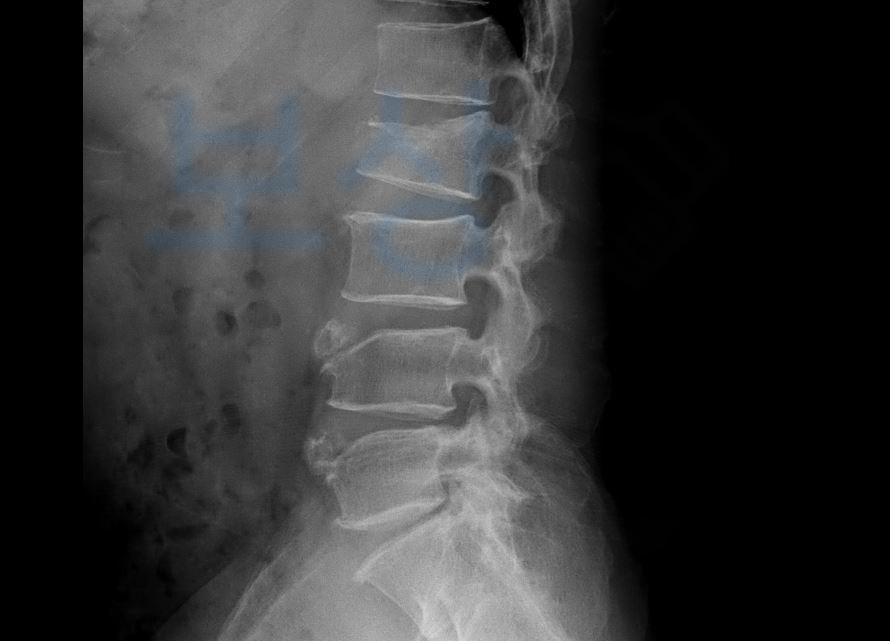

요추2번 압박골절 S32030

척추의 약간의 기형 15%